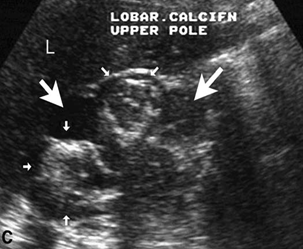

Longitudinal gray-scale ultrasound of the right kidney demonstrates hypoechoic areas (arrows) in the renal cortex suggestive of lobar caseation in this known case of tuberculosis

Longitudinal gray-scale sonography of the kidney in another patient who has renal tuberculosis demonstrates hypoechoic areas of caseous necrosis (large arrows) with dense peripheral calcification (small arrows).